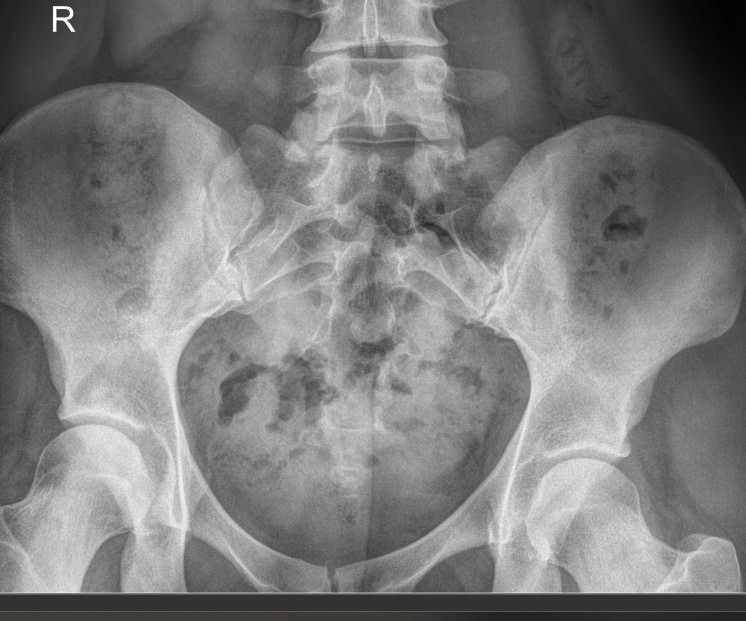

• Отклонение копчика кпереди по отношению к крестцу;

• Изменения в крестцово-копчиковом суставе: уменьшение рентгеновской щели, субхондральный склероз;

• Переломы;

• Новообразования.